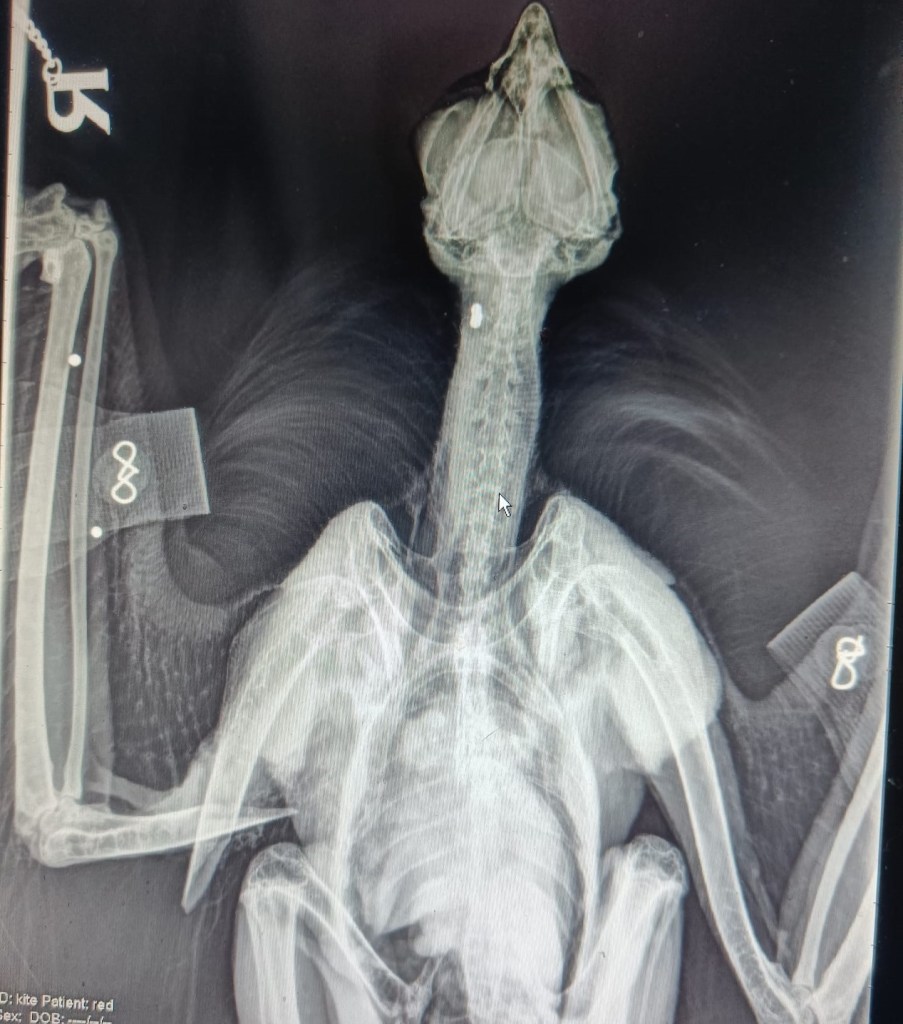

Shelagh’s husband Kenny runs Rathfriland Veterinary Clinic and was unfortunately called upon when Pink 6V was found injured. “Initially we could see that the red kite had a severely broken wing and the wound was already infected. The break was so bad that the agonising decision was made to put the bird to sleep.” Given that there was no logical explanation for the break, no wind turbine or overhead wires for example, an X-ray examination was carried out at the veterinary clinic. “It was then that we discovered she had been shot. There were gunshot pellets in her neck and wing. She will likely have broken her wing after a fall from height as a result from shooting”.